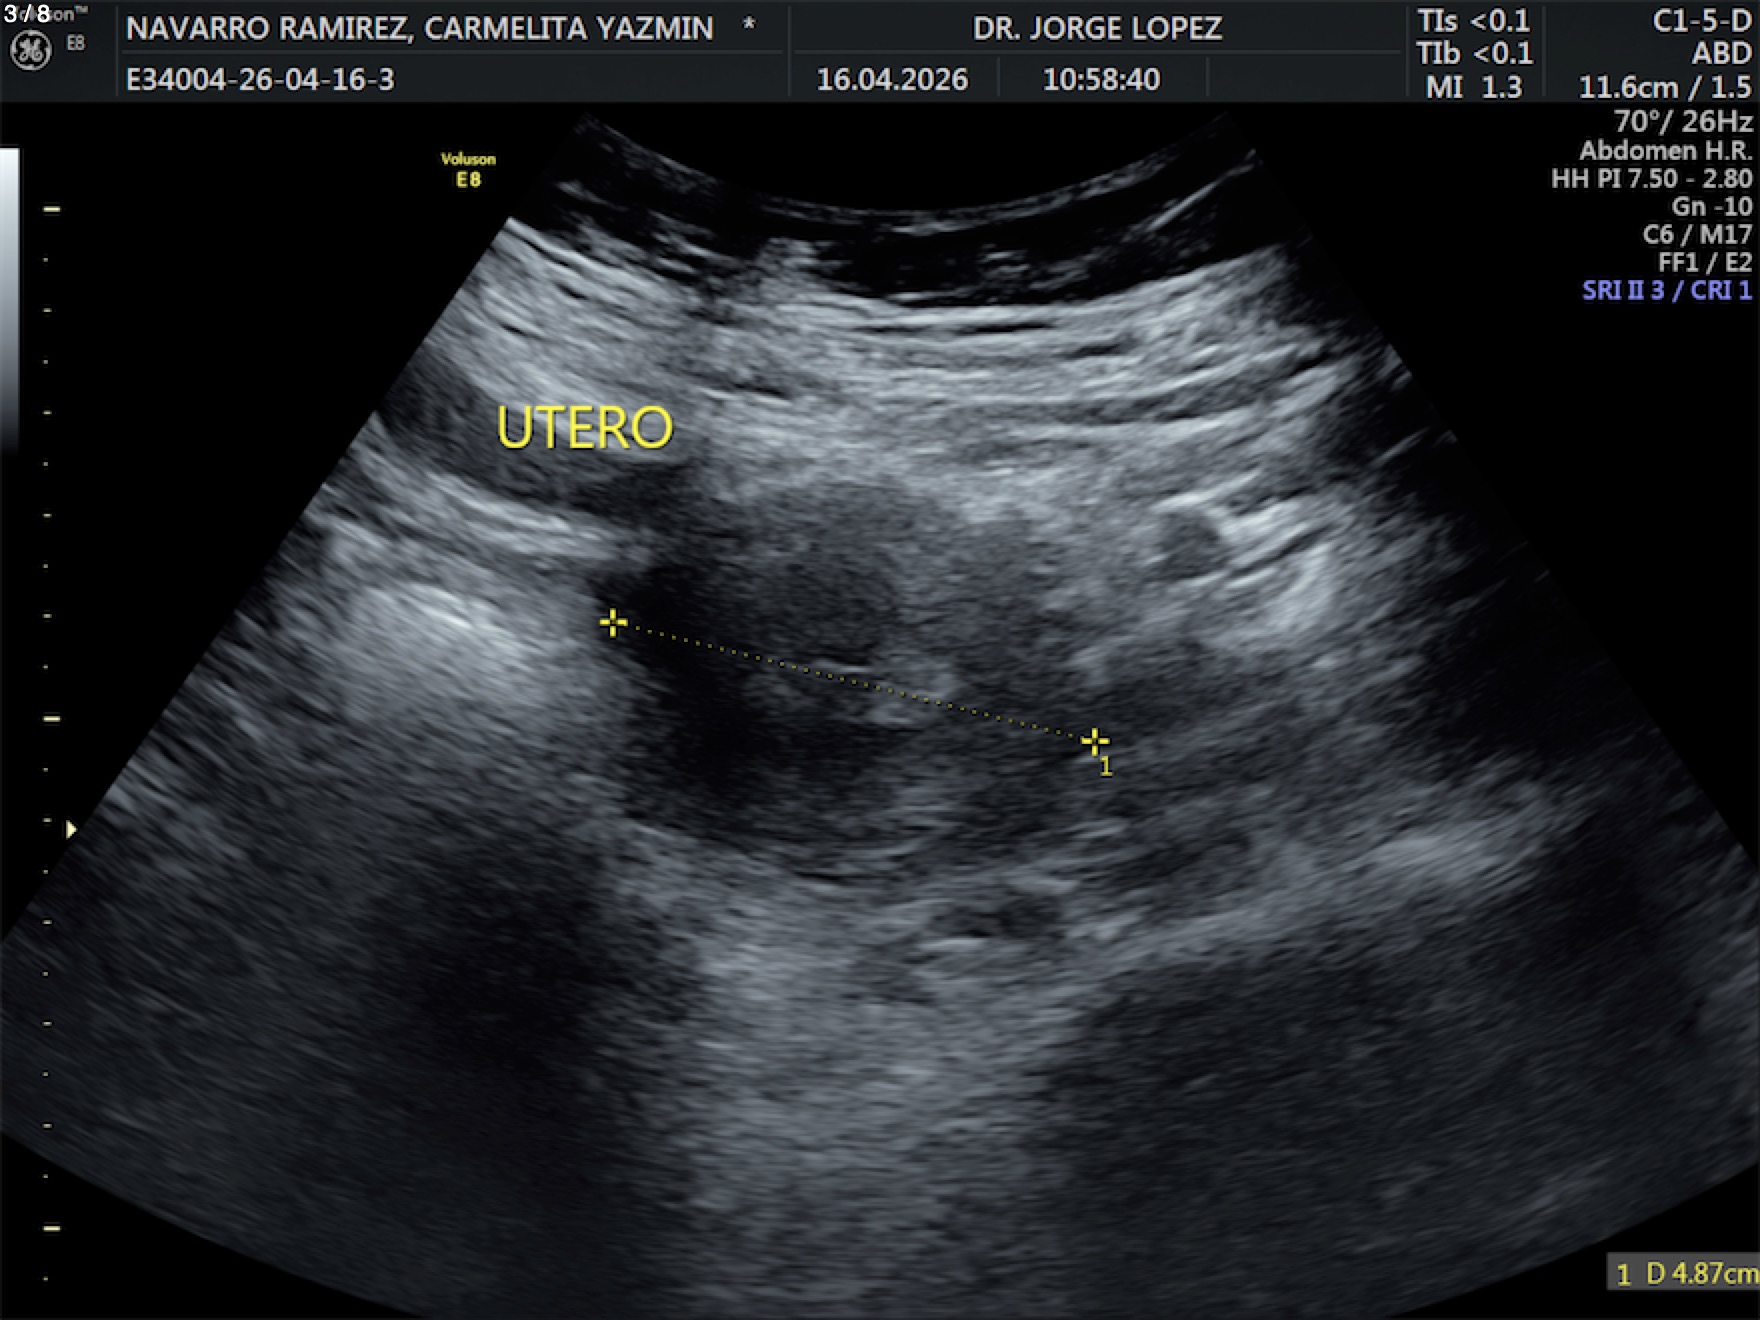

Navarro Ramirez Carmelita Yazmin - Unnamed